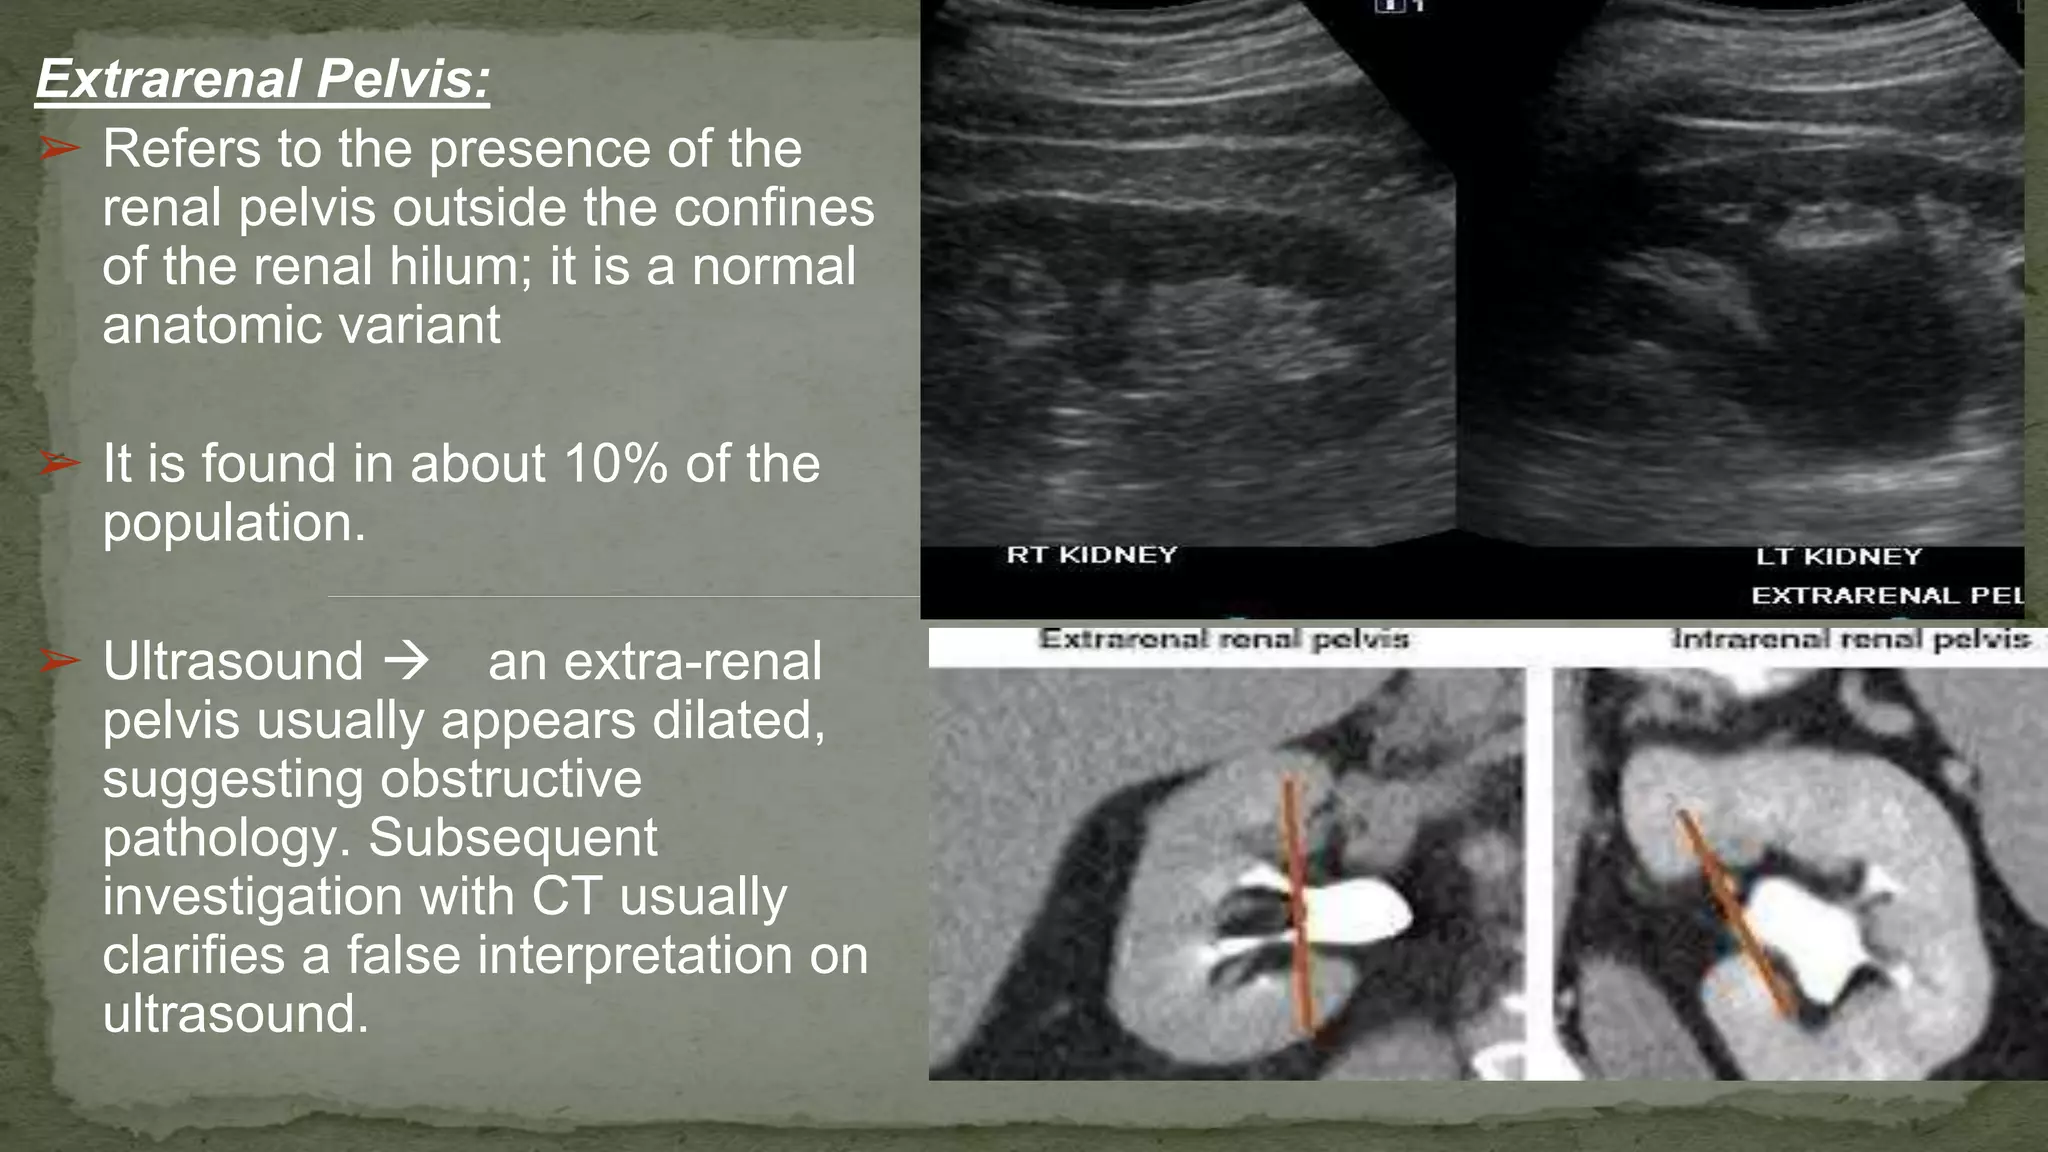

Diagnosing issues related to the extra renal pelvis often involves imaging techniques such as ultrasound, CT scans, or MRI. These imaging studies can provide detailed views of the urinary system, allowing healthcare providers to identify any obstructions or abnormalities in the extra renal pelvis. Treatment options depend on the underlying cause and may include medication, surgical intervention, or other therapeutic approaches.

• Ultrasound: This non-invasive imaging technique uses sound waves to create images of the urinary system, including the extra renal pelvis. It is often the first-line diagnostic tool for evaluating kidney and ureteral issues.

• Computed Tomography (CT) Scan: CT scans provide detailed cross-sectional images of the body, allowing healthcare providers to identify obstructions, tumors, or other abnormalities in the extra renal pelvis.